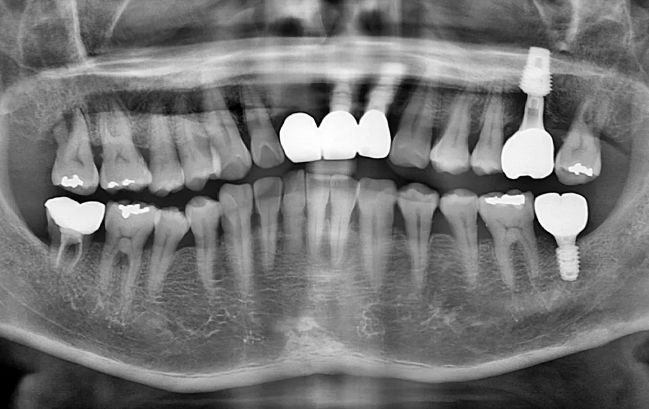

50대 남성, 원데이 수면 전체 임플란트 9개 식립